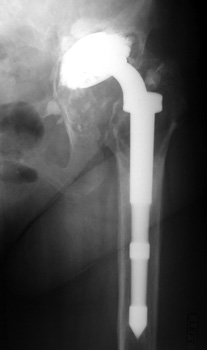

Polyethylene cup dislocation. AP radiograph demonstrates eccentric positioning of femoral head in cup with subtle curvilinear density inferiorly corresponding to dislocated polyethylene liner. Arthrographic spot film demonstrates contrast outlining the polyethylene liner. Model of total hip replacement components positioned with polyethylene liner dislocated.